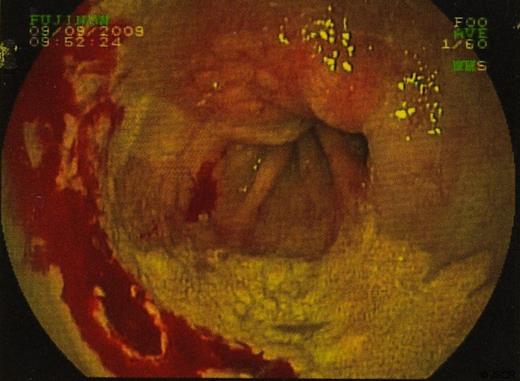

Biopsies were taken and sent to histopathology. In some sections the cells viewed had small bland nuclei with foamy cytoplasm. They were negative for mucin stain and negative for epithelial markers. There was no dysplasia or malignancy. This picture was consistent with xanthalasma. Other biopsies of surrounding tissue showed a picture consistent with Barrett’s oesophagus. (Figure 3 & 4)